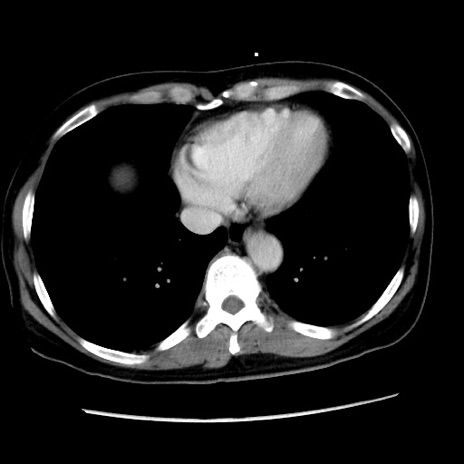

冠状断像

矢状断像